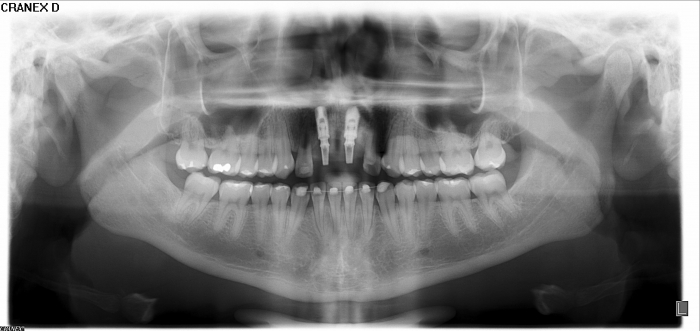

Rx Panorâmico dos implantes com prótese provisória

Protese Provisória sobre os implantes